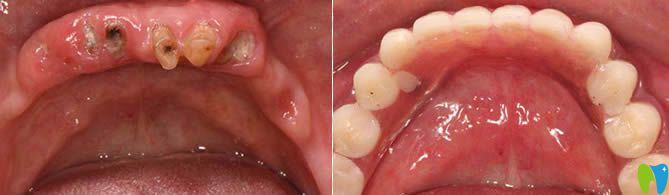

1、60歲老人全口種植牙前后對(duì)比及顧客反饋:

西安諾貝爾口腔李江院長(zhǎng)60歲老人全口種植牙前后對(duì)比<span style=

【顧客評(píng)價(jià)】:這家在我們當(dāng)?shù)厥莻€(gè)老品牌,很早都聽(tīng)說(shuō)比較出名,這次種牙也是我個(gè)咨詢的牙科。很正規(guī),環(huán)境也很舒適,我是早上檢查完,下午就完成了全口種植牙,感覺(jué)諾貝爾的種牙技術(shù)很靠譜,給醫(yī)生們點(diǎn)贊。